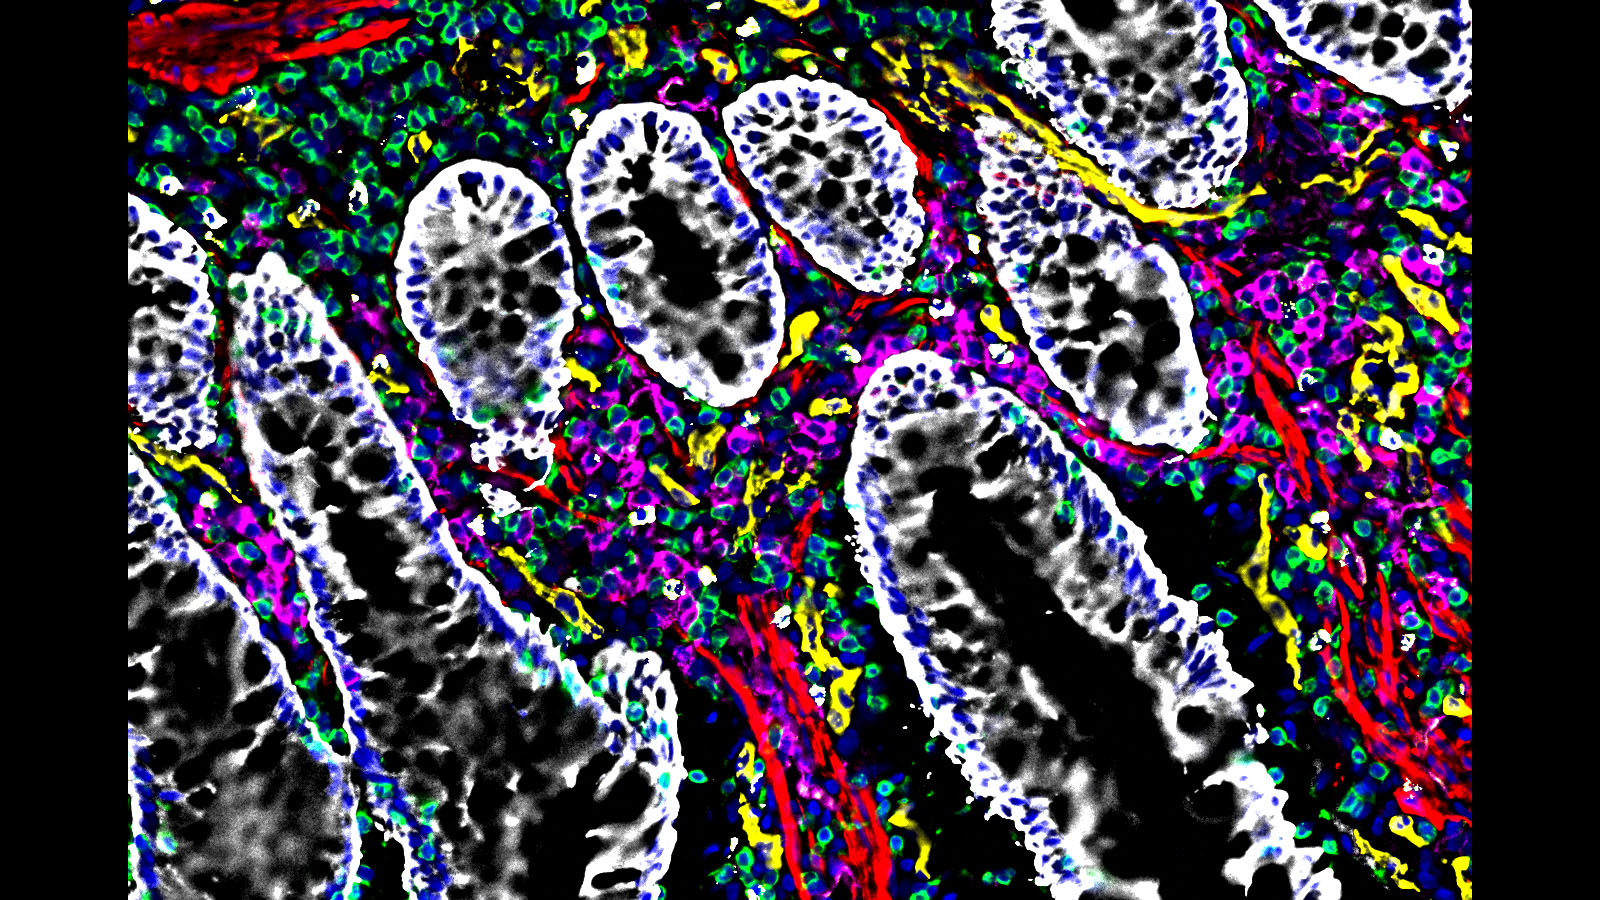

MACSima image of tonsils, courtesy of Drs. Werner Muller and Andreas Bosio at Miltenyi Biotec